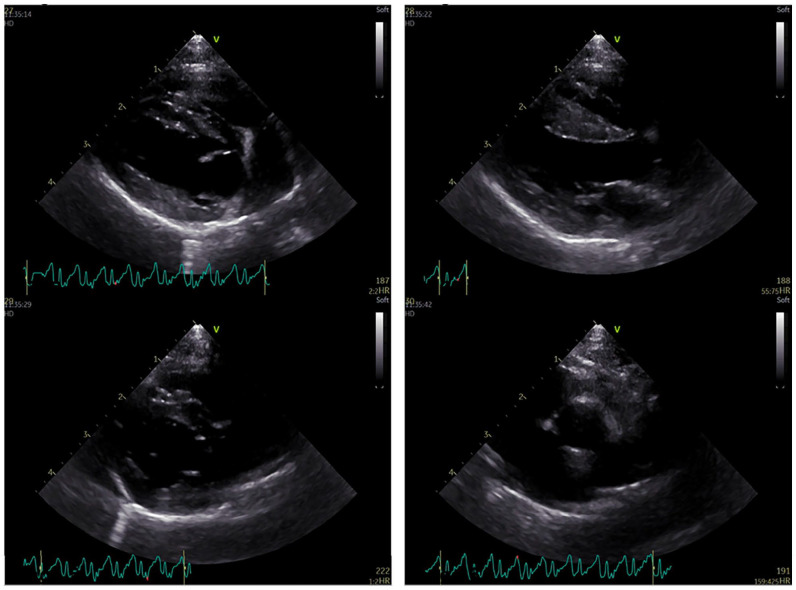

Case summary: A 6-month-old male entire domestic shorthair cat was presented to the ophthalmology department for nasolacrimal duct cannulation and flushing, and castration under general anaesthesia. On pre-anaesthetic assessment, the cat had a heart rate of 90 beats/min (bpm). Clinical examination was unremarkable, although the cat appeared stressed. The echocardiogram was within normal limits. An ambulatory electrocardiogram (ECG) monitor was fitted overnight, and analysis of the ECG revealed a sinus rhythm with a lower than normal heart rate. The mean 1 min rate was 98 bpm. There was a slower than normal sinus rhythm and frequent ventricular escape beats. Differential diagnoses included increased vagal tone and sinoatrial node dysfunction (SND). The latter was suspected as the cat demonstrated signs of stress although an atropine response test was not performed.